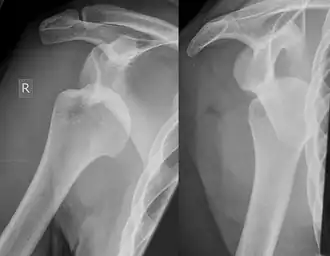

![]() Luxación de hombro derecho con lesión de Hill Sachs | ||

Una lesión de Hill Sachs, también llamada fractura de Hill Sachs, es una depresión cortical en la parte posterolateral de la cabeza humeral.[1] Sucede a causa de la impactación de la cabeza humeral contra el reborde glenoideo anteroinferior al producirse una dislocación anterior del hombro.

La lesión se asocia exclusivamente con dislocaciones anteriores del hombro.[3] Cuando se desvía de la cavidad glenohumeral, la cabeza del húmero (relativamente pequeña para el espacio de la articulación) impacta contra el límite anterior del glenoide. El resultado es un achatamiento del aspecto posteromedial de la cabeza humeral. El mecanismo de producción de las dislocaciones suele ser traumático, aunque puede variar, especialmente si existe historia de dislocaciones previas. Deportes, caídas, lanzamientos, cualquier tipo de movimiento brusco realizado con el hombro puede ser causa de dislocaciones.

La lesión de Hill Sachs puede encontrarse hasta en el 92 % de las dislocaciones anteriores recurrentes. La prevalencia general en las dislocaciones es del 35-76 %.[4] Su presencia, por lo tanto, puede ser utilizada como marcador de que ha existido una dislocación aun cuando el húmero haya vuelto a su posición original.

La mayor parte de estas fracturas se encuentran a través de estudios radiológicos convencionales. Una radiografía posteroanterior con el brazo en rotación interna ofrece una buena visión del defecto, mientras que visiones axilares con el brazo en rotación externa tienden a ocultarlo. La sensibilidad y especificidad de la radiografía se encuentra en un 65 % y 67 %, respectivamente. La ultrasonografía también ha demostrado ser un método útil para identificar esta lesión, con una sensibilidad del 96 % y una especificidad del 100 %.